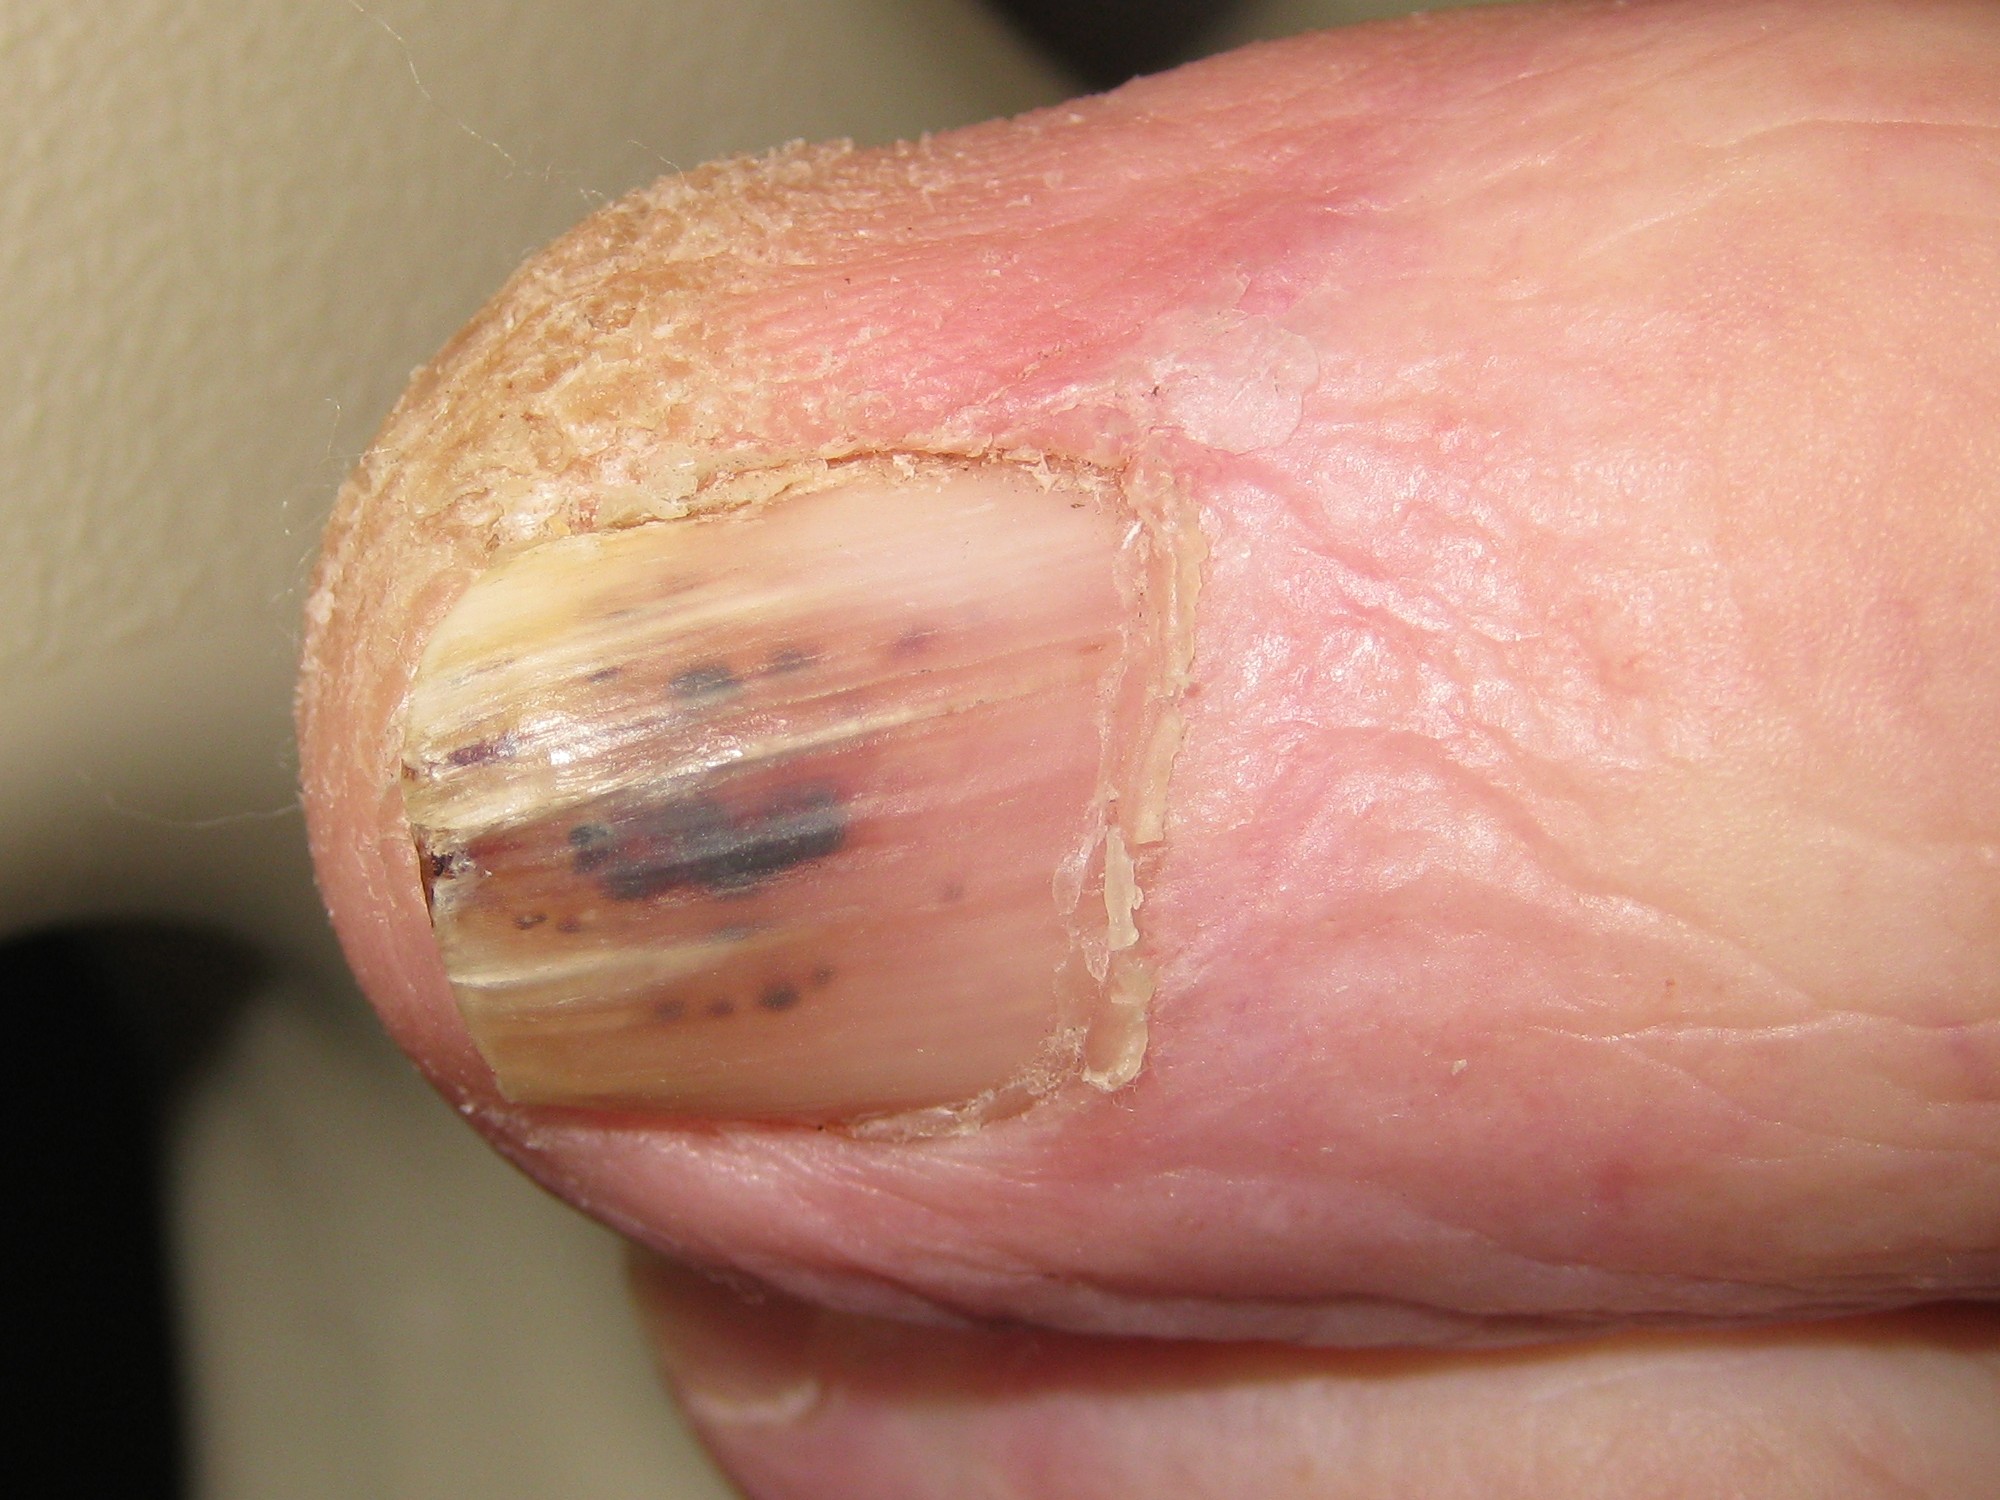

Splinterbloedingen in de nagel (splinter haemorrhages, hemorrhages, splinter bleeding) zijn kleine bloedstolsels of erytrocyten extravasaties onder de nagel, meestal langwerpig. Ze kunnen zowel proximaal als distaal voorkomen. Splinterbloedingen kunnen voorkomen bij een bacteriƫle endocarditis en bij vasculitis, maar ze kunnen ook spontaan ontstaan zonder duidelijke oorzaak, of door trauma of antistolling (zie tabel). Bij endocarditis zijn er soms ook rode niet wegdrukbare laesies in de handpalmen of voetzolen (Janeway lesions genoemd). Ook in de nagelriem kunnen splinterbloedingen voorkomen door beschadigingen van de capillairen ter plaatse, vooral bij auto-immuunziekten. Dit kan worden beoordeeld met de dermatoscoop (capillairoscopie).

DD: subunguaal hematoom, subunguaal melanoom, melanonychia (zie onder nagelafwijkingen).

- psoriasis

- onychomatricoma